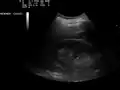

Ultrasound of liver (left side of the image) and right kidney (right side of the image) and Morison's pouch, not containing fluid Ultrasound of liver (left side of the image) and right kidney (right side of the image) and Morison's pouch, not containing fluid